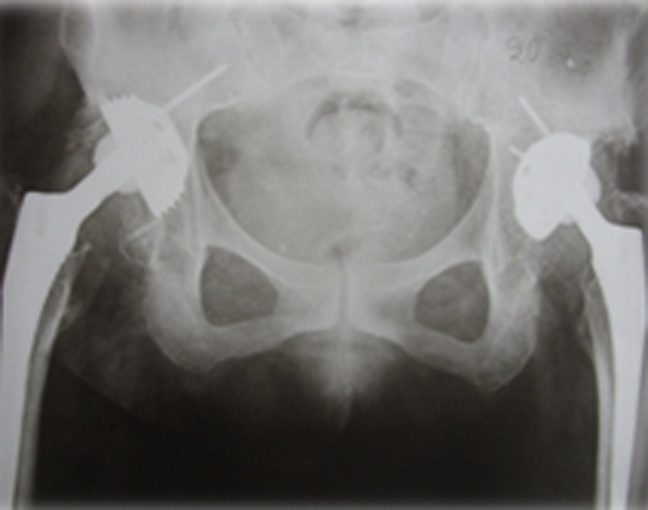

Η θεραπεία σ΄ αυτά τα παραμελημένα εξαρθρήματα είναι χειρουργική και ονομάζεται αρθροπλαστική, δηλαδή αντικατάσταση της κεφαλής του μηριαίου με μεταλλική. Όμως για να λειτουργήσει σωστά, πρέπει η νέα κεφαλή να κατέβει στη θέση της φυσιολογικής κοτύλης και αυτό κάνει την εγχείρηση αρκετά δύσκολη, λόγω βράχυνσης που έχουν υποστεί μύες και νεύρα.

Το εξαρθρηματικό σκέλος, λόγω περιορισμένης φόρτισης, είναι συνήθως πιο αδύνατο σε εμφάνιση από το φυσιολογικό και το κόκκαλο πιο στενό-μικρό. Γι΄ αυτό και έχουν κατασκευασθεί ειδικές «προθέσεις» για τα χειρουργεία των εξαρθρηματικών ισχίων.